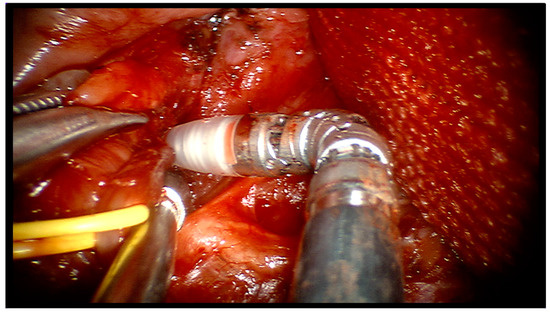

TORS-S—Docking of the da Vinci Si system was carried out according to the approach explained in the aforementioned article [14]: the mouth was held open using a lateral mouth gag which was introduced inside the patient’s oral cavity, the patient’s cart with the three robot arms was docked behind the head of the patient at an angle of 30°, on the side opposite to the affected gland (thus on the left side, in this case), and a downward-facing 30° HD robotic endoscope was placed into the robotic endoscope holder. Two robotic 5 mm instruments, a Maryland dissector and a monopolar cautery with spatula tip were placed into arms 1 and 3 according to the side of the stone. A square-shaped tongue retractor covered by rough gauze was positioned to retract the tongue to the contralateral side and to flatten the oral floor. The location of the stone was carefully marked on the mucosal surface by means of palpation and its borders were drawn over the oral floor’s mucosa with a dermal marker. The first operator sat at the console while surgeon’s aid sat at the patient’s head contralateral to the affected side and was responsible for suction, tongue retraction and pushing up of the submandibular region. Using monopolar cautery, an oblique incision was made just over the calculus area, on the oral pelvis, and prolonged caudally and cranially. The surgical incision was then carefully deepened, preserving both the lingual nerve, by moving it laterally, and the Wharton’s duct (Figure 2).

Figure 2.

Robotic dissection of right oral hemipelvis identifying noble structures.